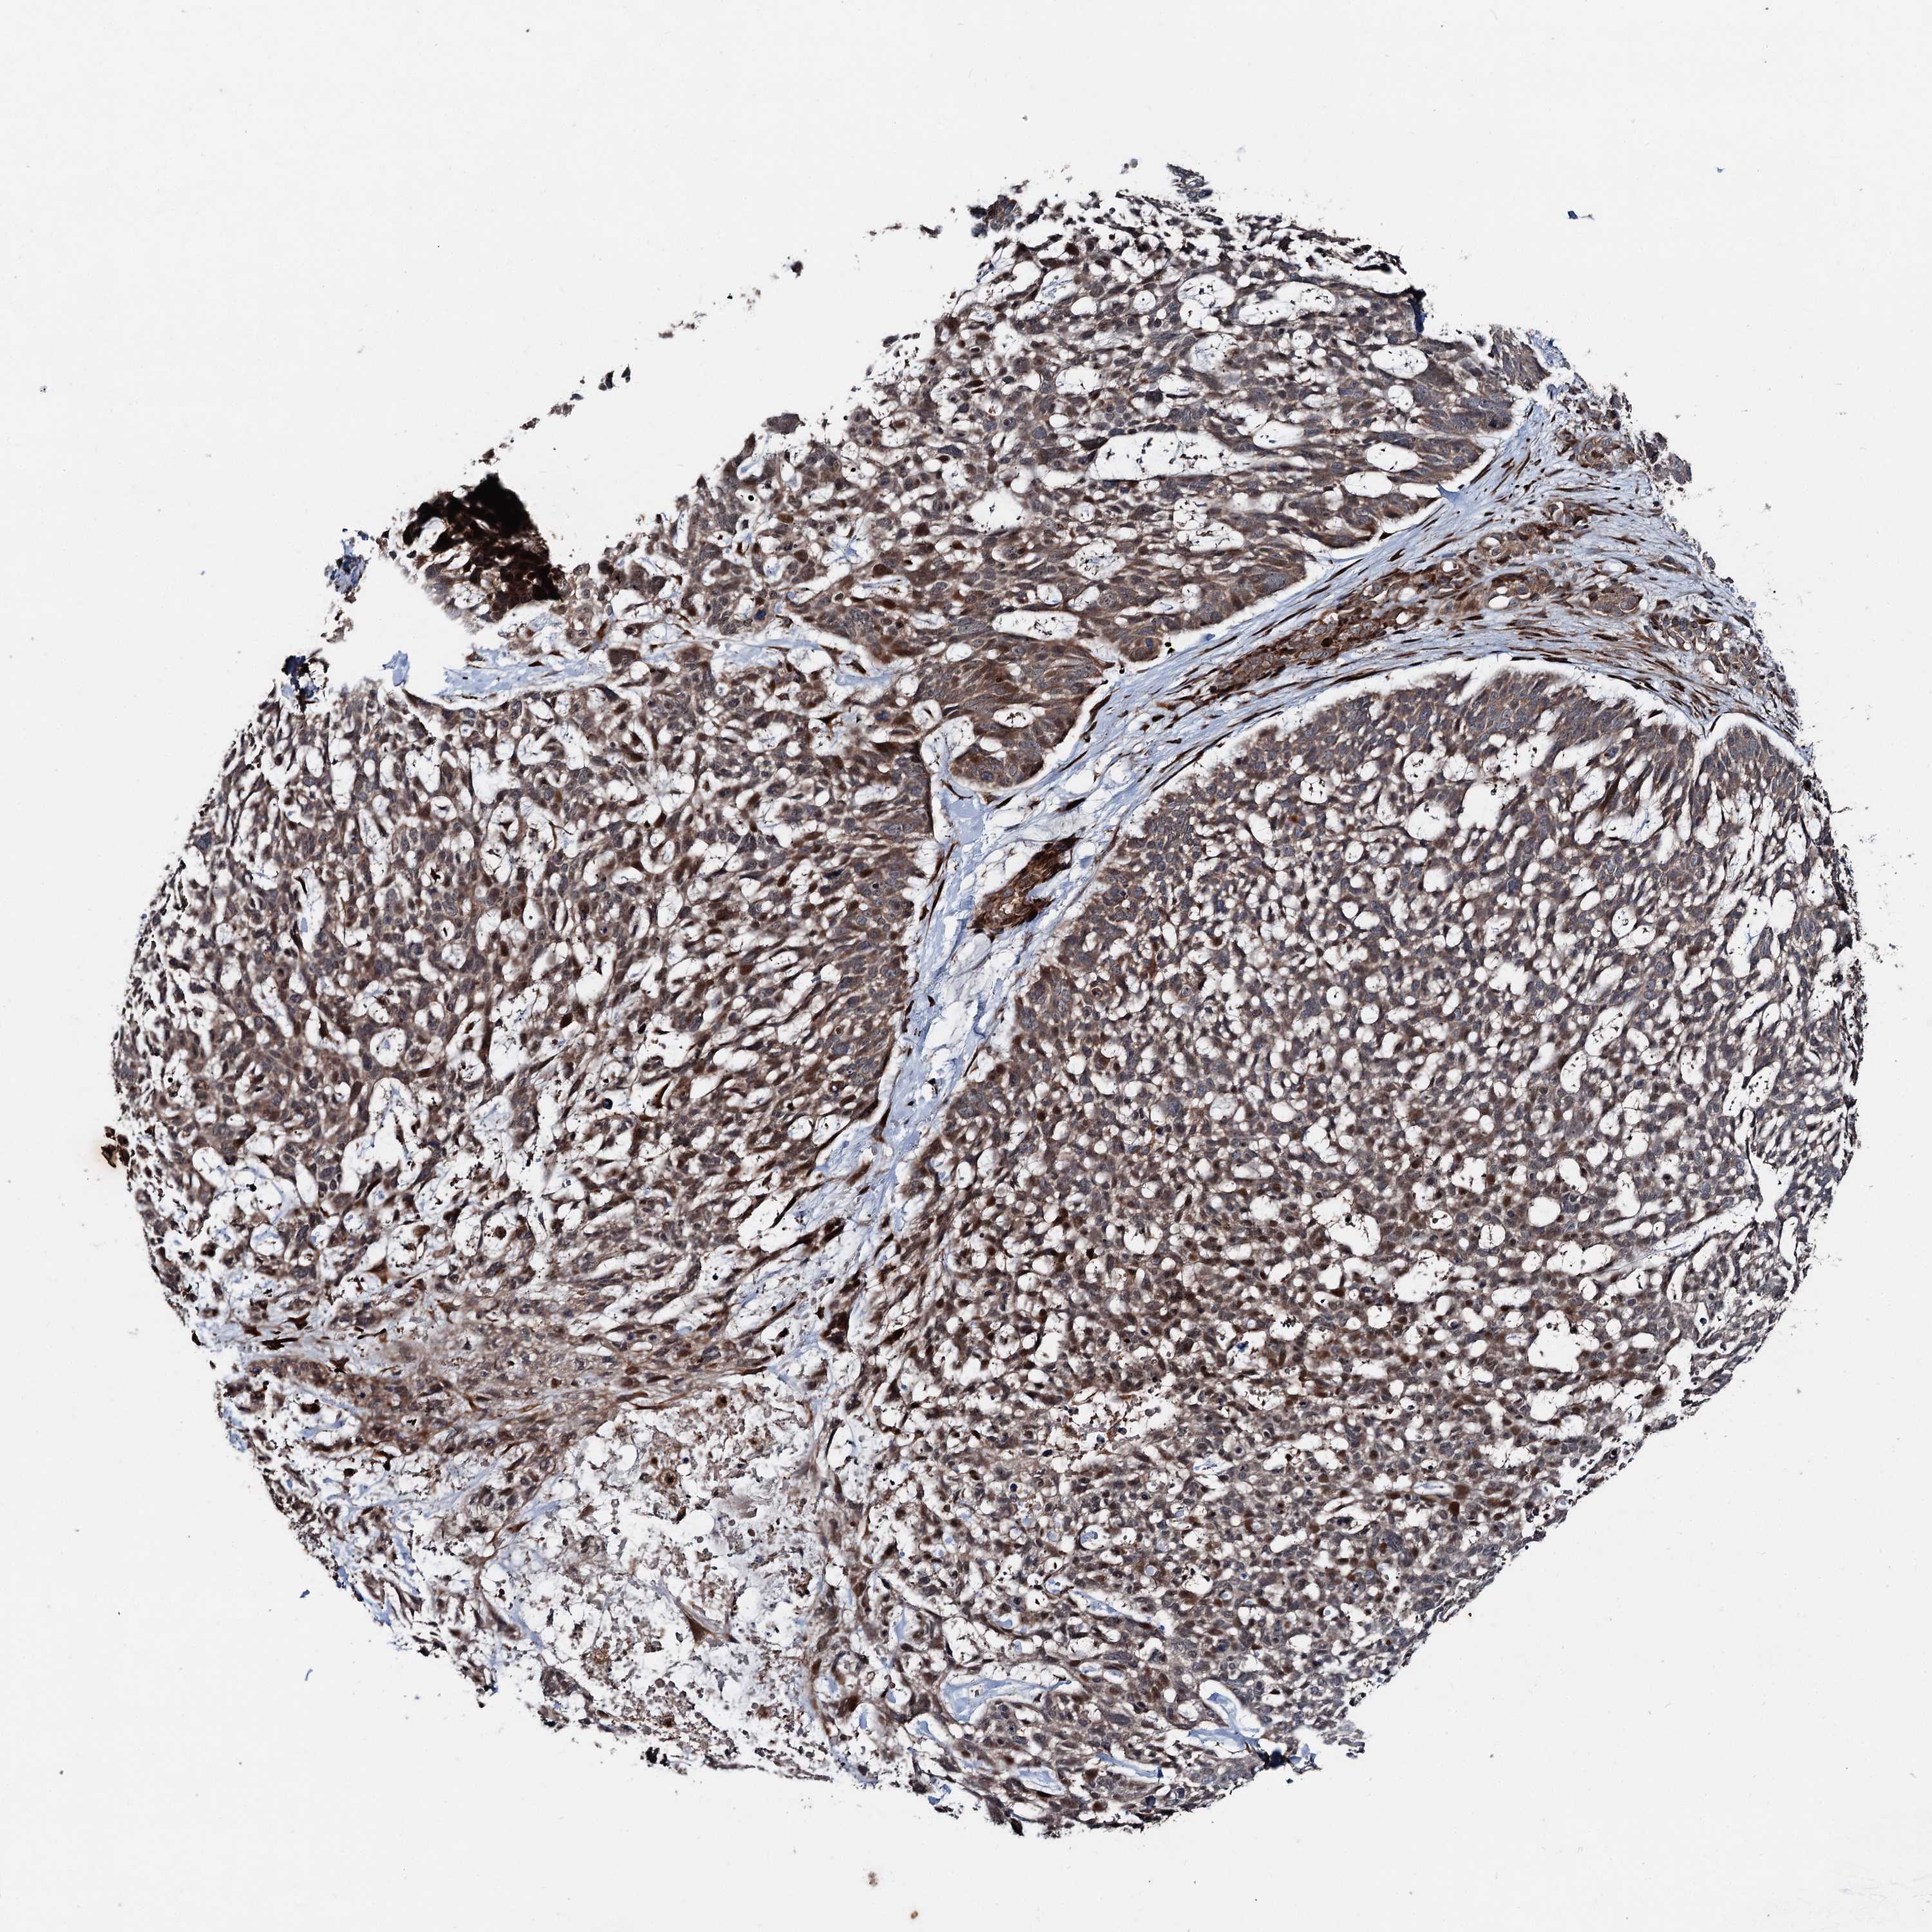

SKIN CANCER - Protein expressioni

A mouse-over function shows sample information and annotation data. Click on an image to view it in a full screen mode. Samples can be filtered based on level of antibody staining by selecting one or several of the following categories: high, medium, low and not detected. The assay and annotation is described here.

Each image is clickable and will lead to virtual microscopy that enables deeper exploration of all samples and also displays staining intensity scores, fraction scores and subcellular localization as well as patient and tissue information for each sample.

Antibody HPA038541

Staining

Medium

Squamous cell carcinoma, NOS